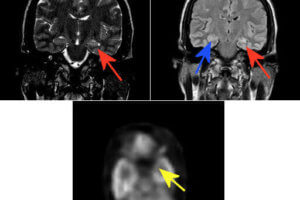

Hypothalamic Hemartoma and Gelastic Seizures

The MR images show an abnormal growth hanging down from the hypothalamus. This is a hypothalamic hemartoma, which in some cases can be a type of grey matter heterotopia within the tuber cinereum.... Read more »